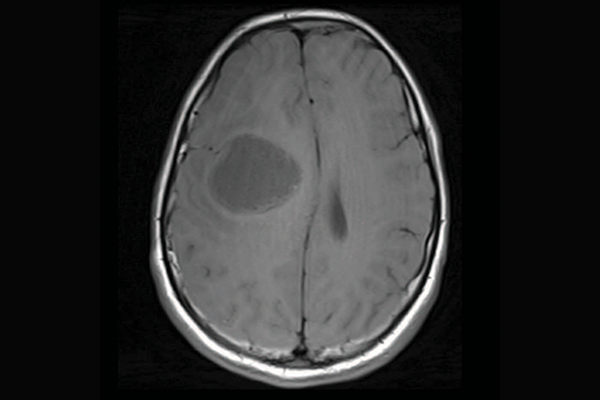

High-grade gliomas are a group of aggressive brain tumours and one of the deadliest tumours in children and young adults. In some children, the tumours are driven by mismatch repair deficiency (MMRD), which is characterized by hypermutation (a large and quickly accumulating number of mutations in tumour cells) and resistance to standard treatments such as chemotherapy and radiation.

priMMRD-3: The immune-cold

Accounting for the remaining 19 per cent of gliomas studied, these tumours have MMRD mutations and a variation in the IDH1 gene. While they often have poor responses to immunotherapy alone, SickKids clinicians and scientists are working toward a clinical trial to pair targeted immunotherapies with a IDH1 inhibitor to provide more tailored care for this subgroup of patients.